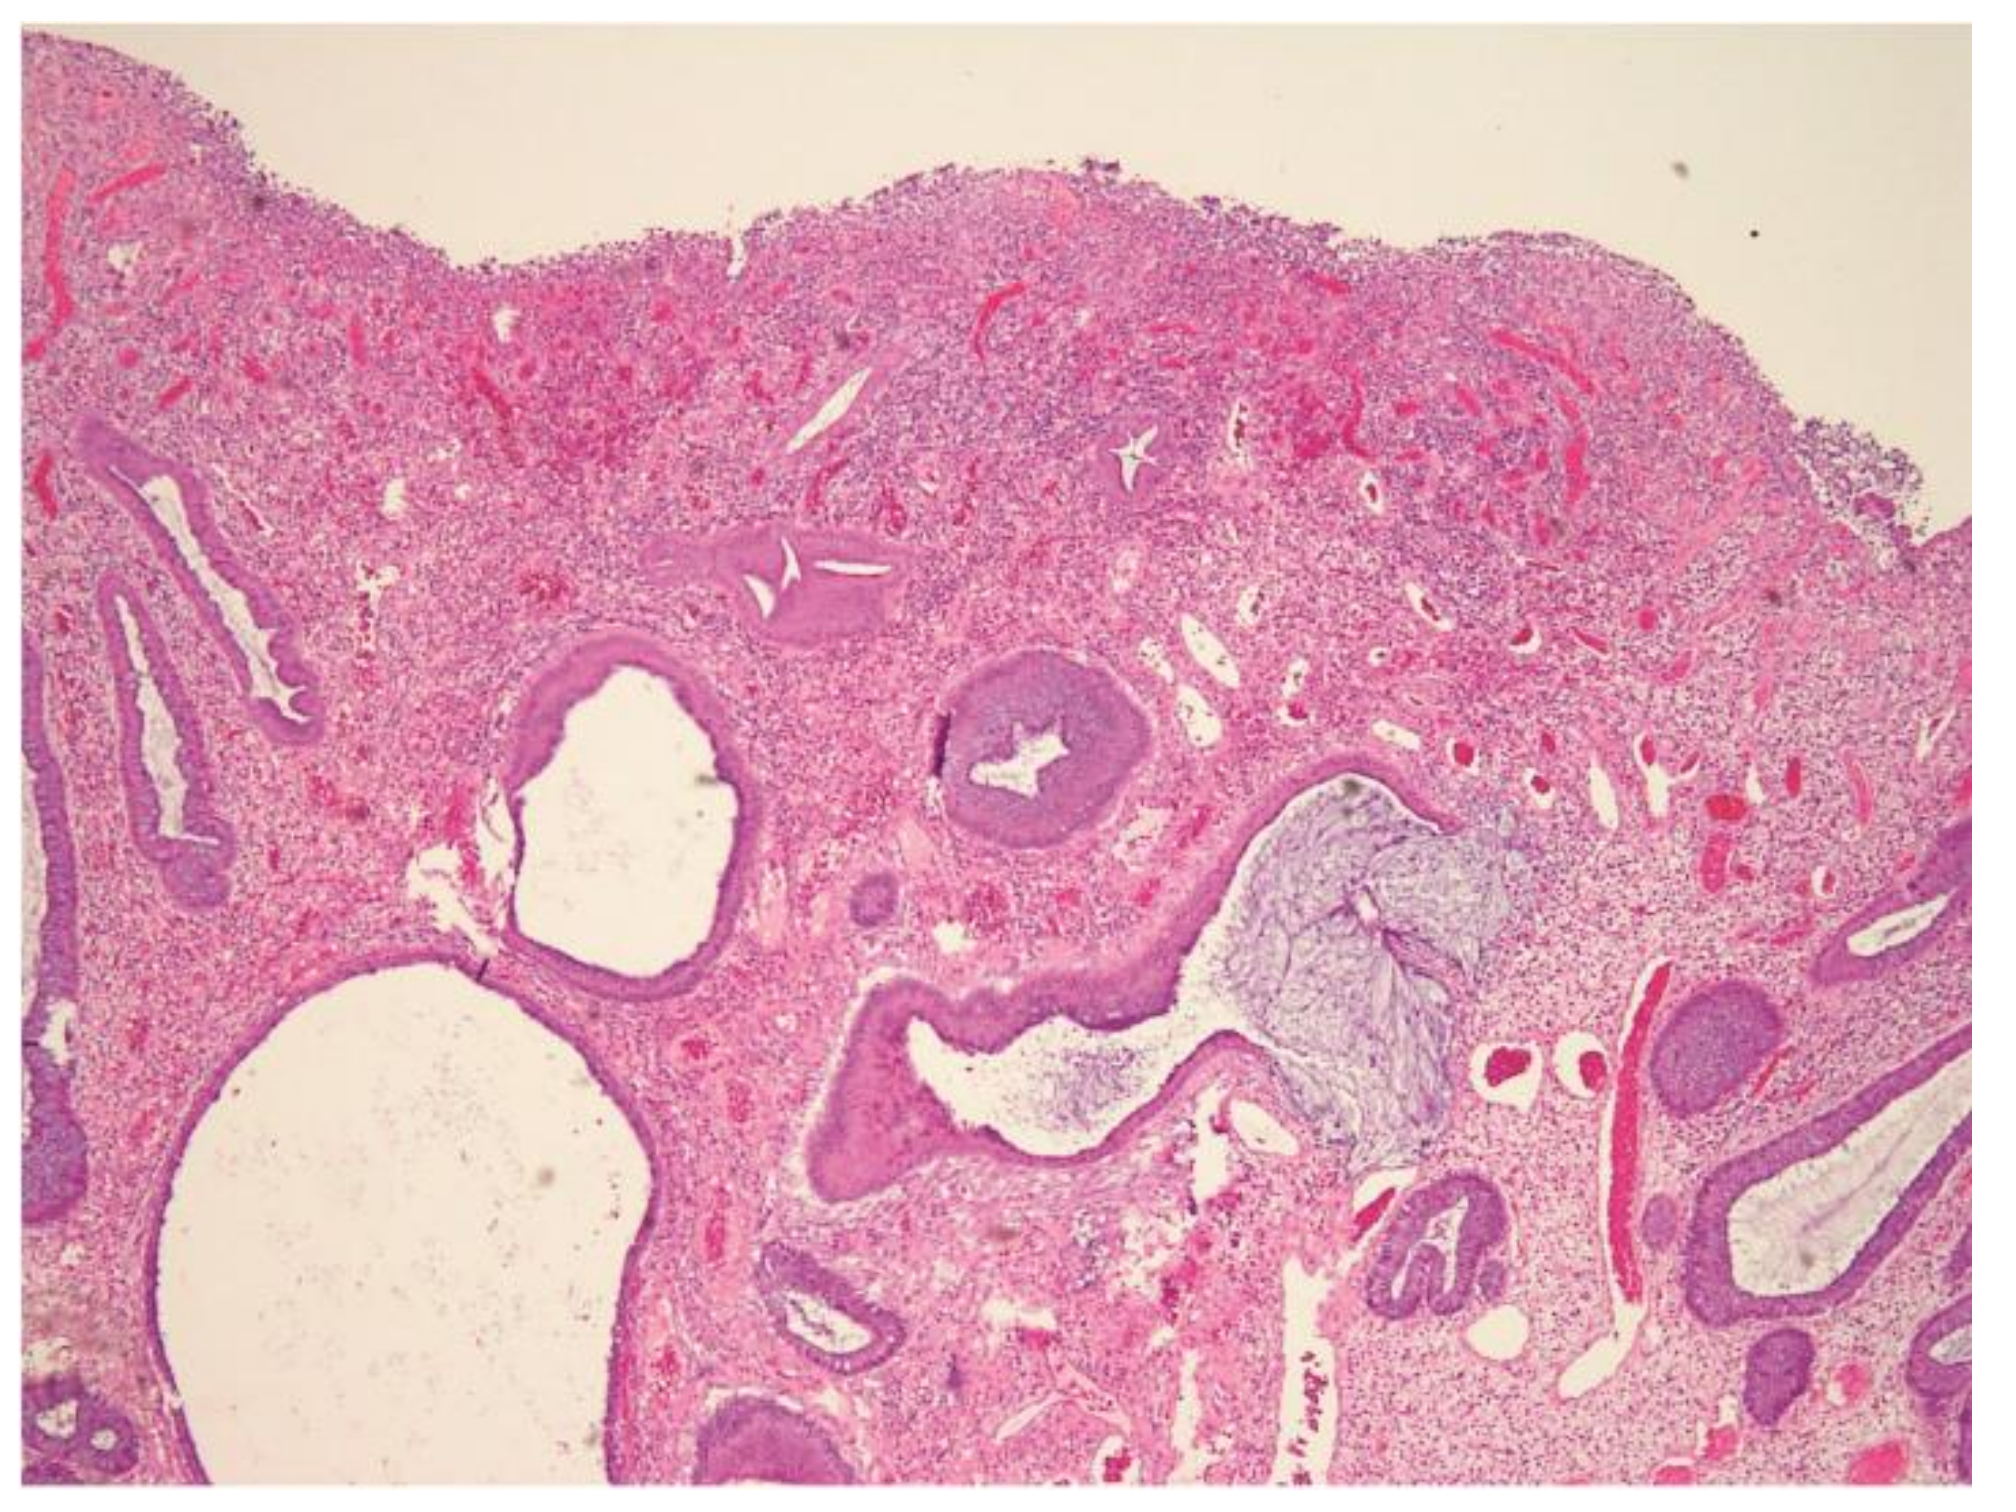

Endoloop-Assisted Polypectomy for a Symptomatic Giant Colonic Polyp in a Pediatric Patient

2. Laboratory Results and Treatment

3. Discussion